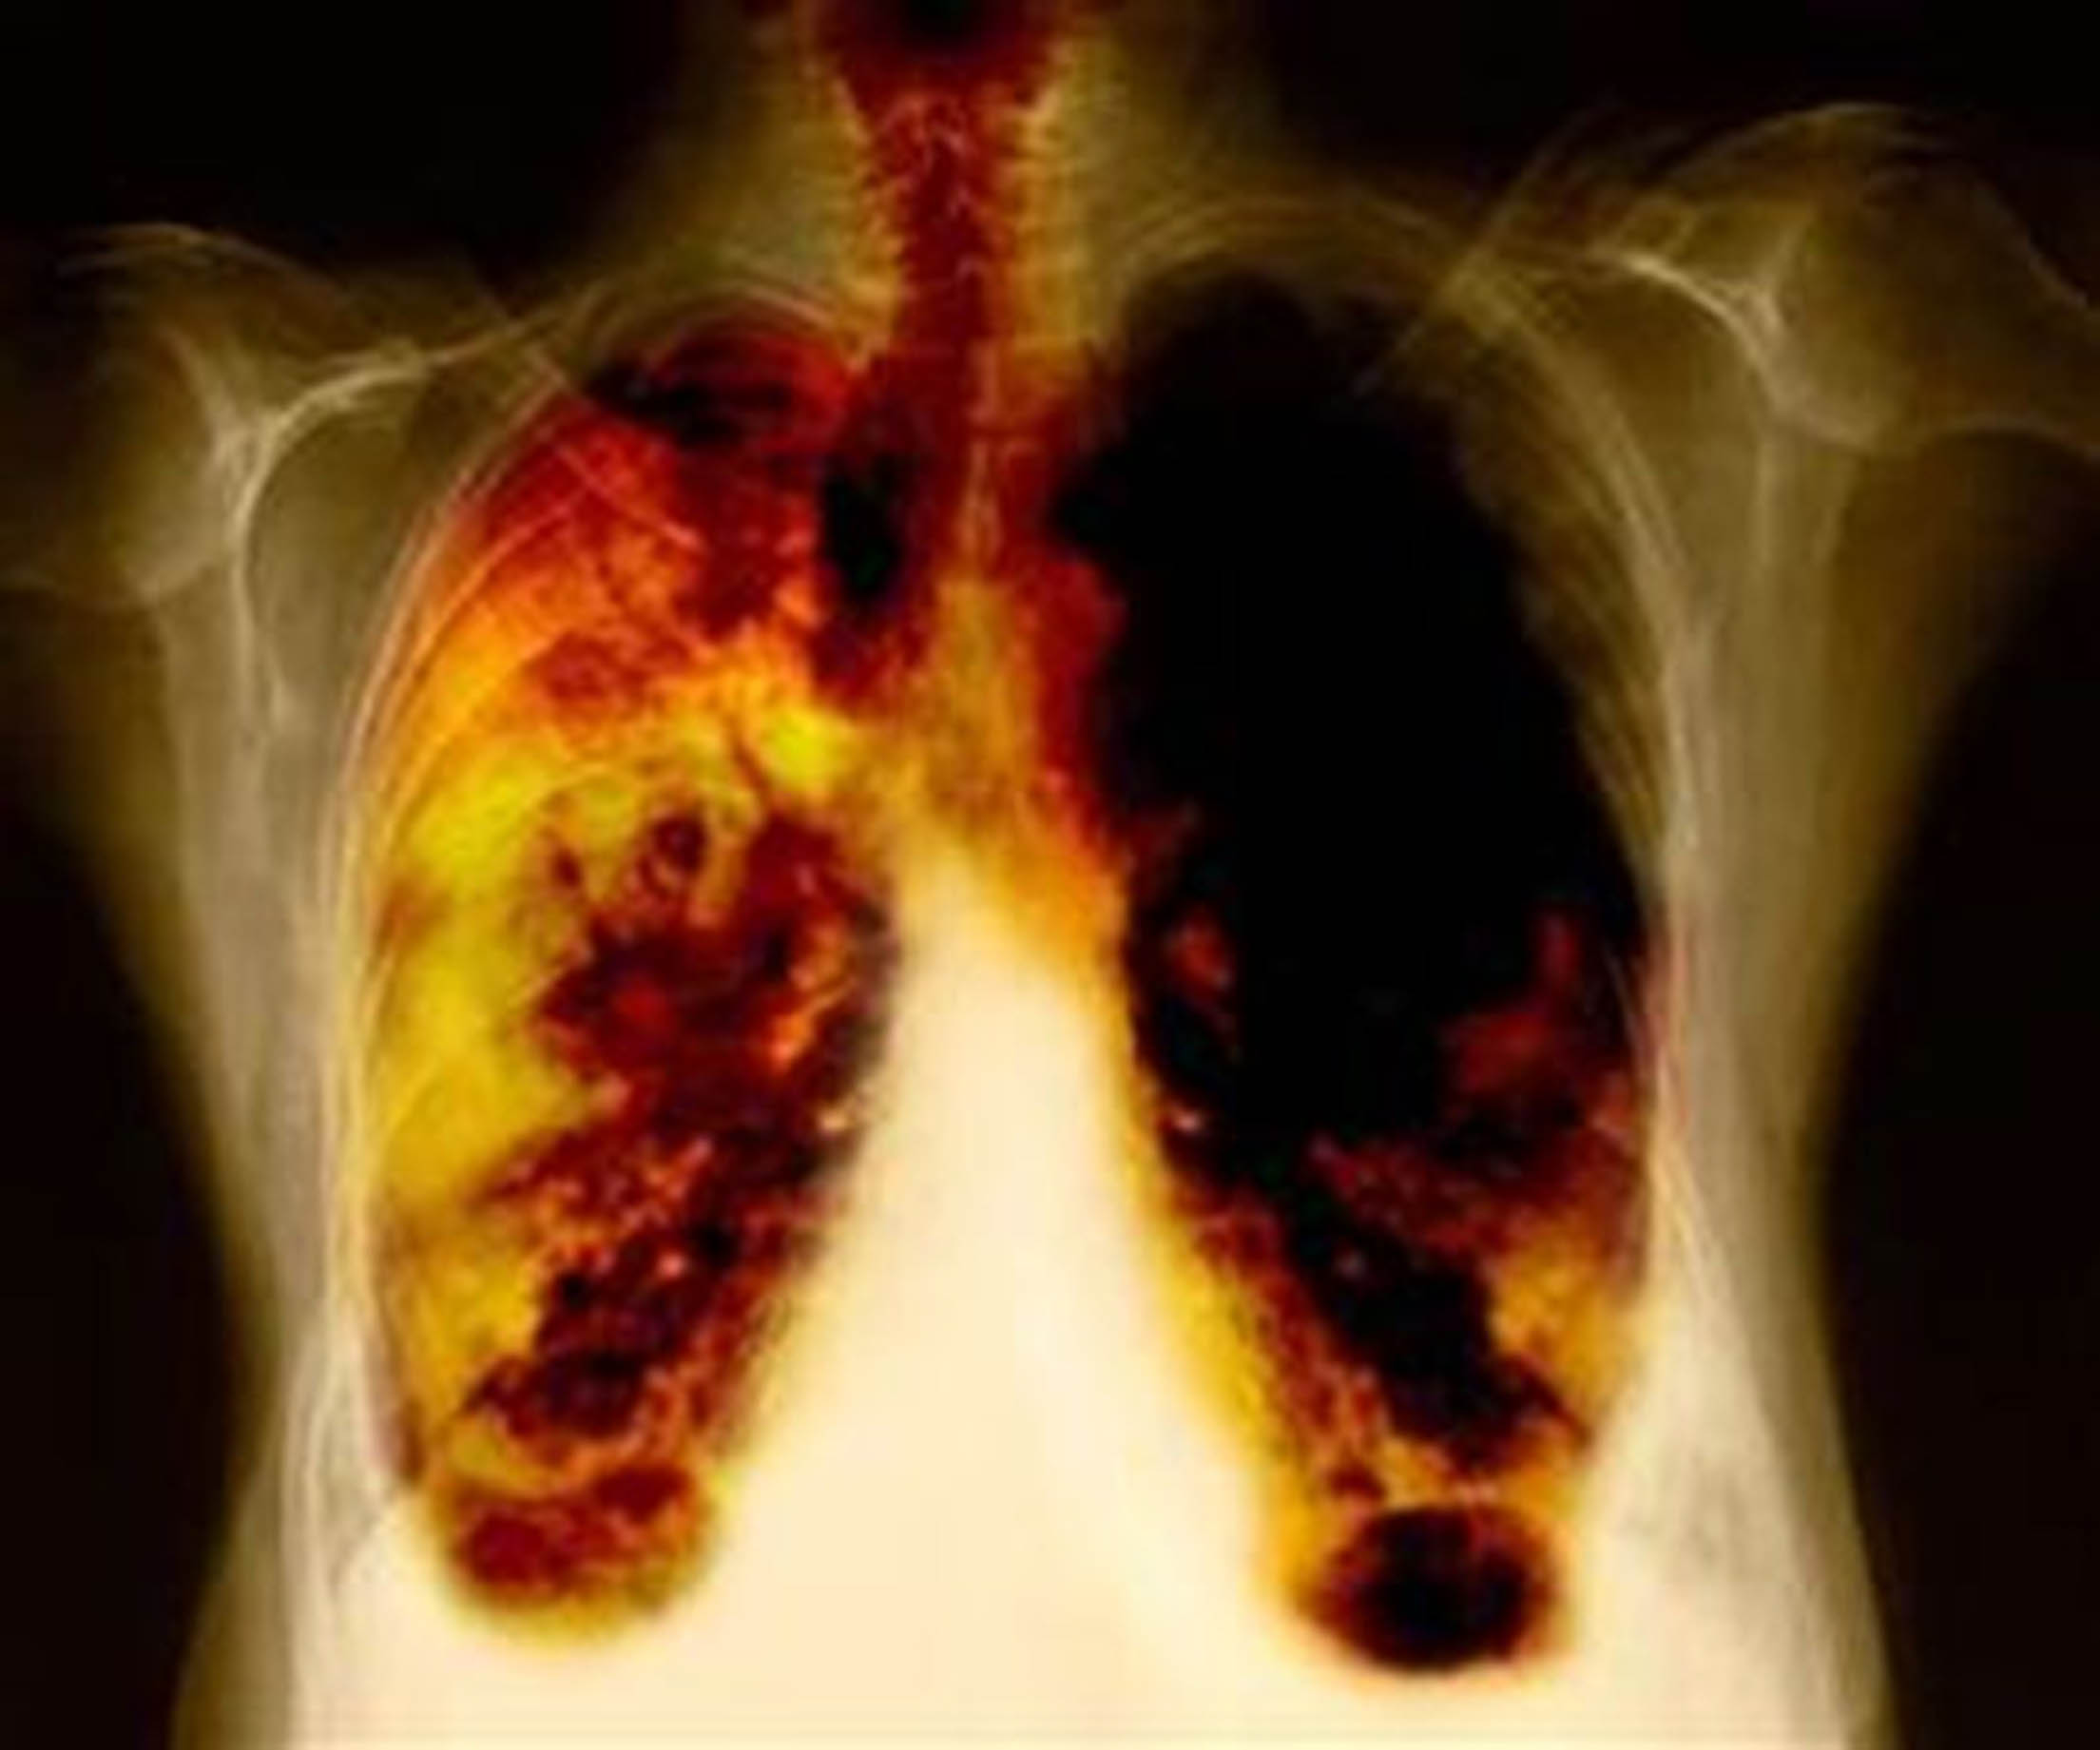

La incidencia del cáncer de pulmón ha crecido un 17% en los últimos diez años, “espoleada por el mayor número de casos en mujeres, por lo que urge una actuación global para frenar este tumor”, asegura el doctor Mariano Provencio, presidente de la entidad y jefe de Oncología del Hospital Puerta del Hierro de Madrid. Este cáncer es el que registra las peores cifras de mortalidad.

La incidencia del cáncer de pulmón ha crecido un 17% en los últimos diez años